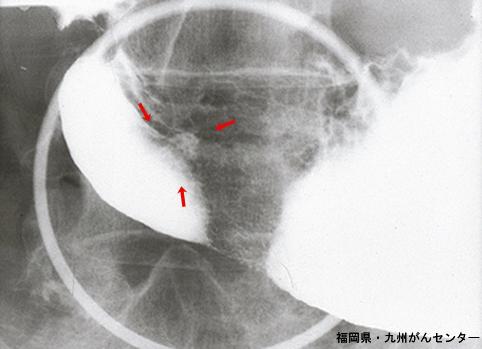

clasificación del pacienteTumor Epitelial Benigno/Adenoma

parte(separada por órganos)estómago(región)/antro

método de exámenRayos X

clasificación ectoscópica de tumoresTipo 0(tipo superficial)/Tipo IIc(IIc)

diámetro mayor del tumor10 - 14